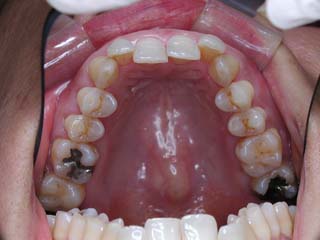

主訴:顎の歪み

診断名:骨格性下顎左方偏位

年齢:24歳

使用した主な装置名:TPB、マルチブラケット装置

抜歯/非抜歯および抜歯部位:非抜歯

治療期間:動的処置1年6か月、経過観察3年

費用の目安:保険適応 自己負担金として30~50万

リスク、副作用:外科手術によるリスク、マルチブラケット治療に伴う歯根吸収など偶発症が発生するリスクがある。

極めて強い側方変位を認めます。前後的・垂直的な問題は見られません。大きなズレであれば、外科的に骨のズレを改善する治療が選択されます。横断的な問題はその他の不正咬合と比較して、解決がかなり難しい事が多いです。治療後の後戻りが頻繁に見られる不正咬合ですので、外科矯正での改善が望ましい場合も多いでしょう。

このケースでは、外科手術は、上顎の傾斜の改善をLeFort1にて、下顎の正中の改善をSSROにて行いました。